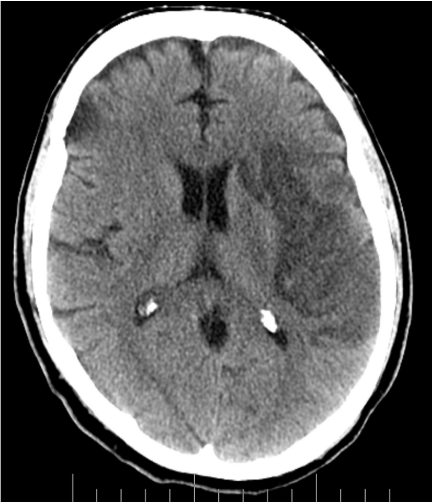

Vital signs on presentation at the outside hospital were: Temperature 38.1 F, Heart Rate of 90-101 beats/minute, Respiratory Rate 20-40 breaths/ minute, mean arterial pressure of 70 mmHg and oxygen saturation of 94% on VentiMask 40%. On examination at our hospital he was found to be tachypneic at 33 breaths/minute requiring Bi-level positive airway pressure (BiPAP), heart rate-106 beats/minute, mean arterial pressure-64 mmHg and oxygen saturation of 90% on VentiMask 40%. He appeared confused and lethargic. Neck exam was positive for jugular venous distension. He had decreased breath sounds bilaterally and the LVAD hum was heard on cardiac exam. On neurologic exam, he did not follow any commands, was aphasic with a right facial droop and had right hemiplegia. On checking with the outside hospital, due to his acute distress and lethargy, a neurologic exam was not performed. Laboratory tests on admission were consistent with hemolysis and acute renal failure (Table 2). LDH was elevated at 3012 (IU/L) up from<500 a week ago. Chest radiography was consistent with pulmonary edema (Figure 1). CT Head revealed a left non-hemorrhagic MCA infarct with mild mass effect and mild midline shift from left to right (Figure 2). Urine in his Foley bag was orange- red in color. A stat echocardiogram (Figure 3) obtained revealed a dilated left and right ventricle and an aortic valve opening every beat that was opening every other beat on his last clinic visit, 3 weeks ago. This further confirmed the working diagnosis of an acute LVAD thrombus complicated by an embolic event leading to the acute ischemic infarct. An emergent Neurology consultation was obtained and after reviewing his physical exam and CT-brain with the Neurology team, the diagnosis of acute ischemic stroke with significant right hemiplegia was confirmed. Since he was outside the recommended treatment window for thrombolytic administration for his acute stroke (9hours against the recommended, the Neurology team recommended against the use of systemic thrombolysis due to the increased risk for bleeding vs. reducing infarct size.

Figure 1 Chest X- Ray at presentation.